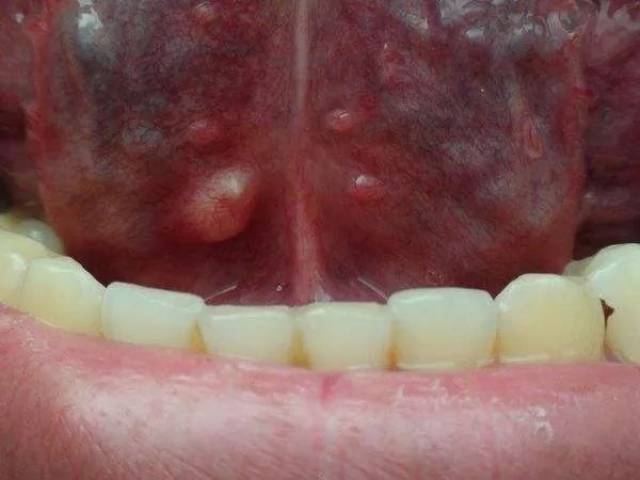

舌尖红色针状肉芽,舌头边缘红色肉芽图

千万别忽视身体这部位的"小疙瘩" 警惕癌变!

病,有干燥脱屑型唇炎,过敏型唇炎,良性淋巴增生性唇炎,肉芽肿性唇炎

舌头边缘红色肉芽图

舌尖边缘小肉芽图片

舌头边缘增生肉芽图片